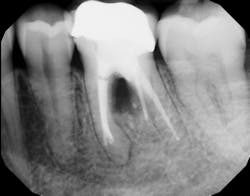

Another advancement in the field of periodontal regenerative medicine has been due to the use of growth factors, proteins, and stem cells. The ability to repair/regenerate a diseased tooth is often dependent upon the extent of the defect, namely the number of bone walls that are left surrounding the tooth. The more bone walls a tooth has left around it (maximum of four), the more blood supply, containment, and space maintenance your graft material will have (figure 5).

Bone defects that have three to four walls missing are the hardest to repair and may be slated for extraction (figure 6). By adding growth-stimulating factors to your regular bone grafts (figure 7), an increase in osteopromotive potential occurs that can have the ability to overcome a deficiency of bone walls.15 Simply stated, your bone graft can become alive, and teeth that were once unable to be repaired now have a chance.

Figure 6: Molar tooth with three walls missing around the palatal root. This tooth would normally be extracted.

Figure 7: Same tooth undergoing periodontal regeneration surgery with anorganic bovine bone (Bio-Oss Collagen, Geistlich Biomaterials) and platelet-derived growth factor (PDGF)